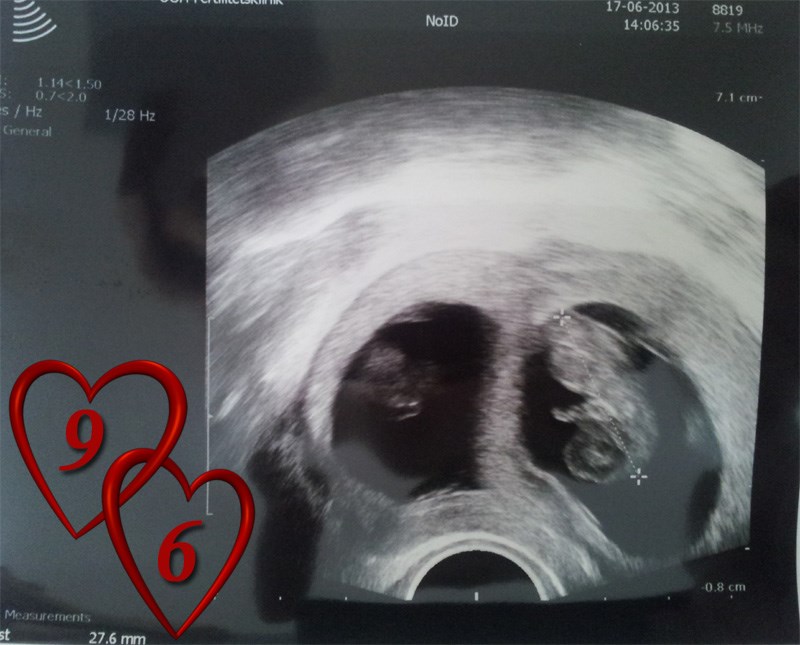

Først et billede af tvilling 1, som måler 27.6 mm.

Man kan jo sagtens se en forskel på de to og til trods for der var hjerteblink hos dem begge i uge 8+0 og tvilling 2 var 2 mm kortere end tvilling 1 - lader det til at den er gået til..